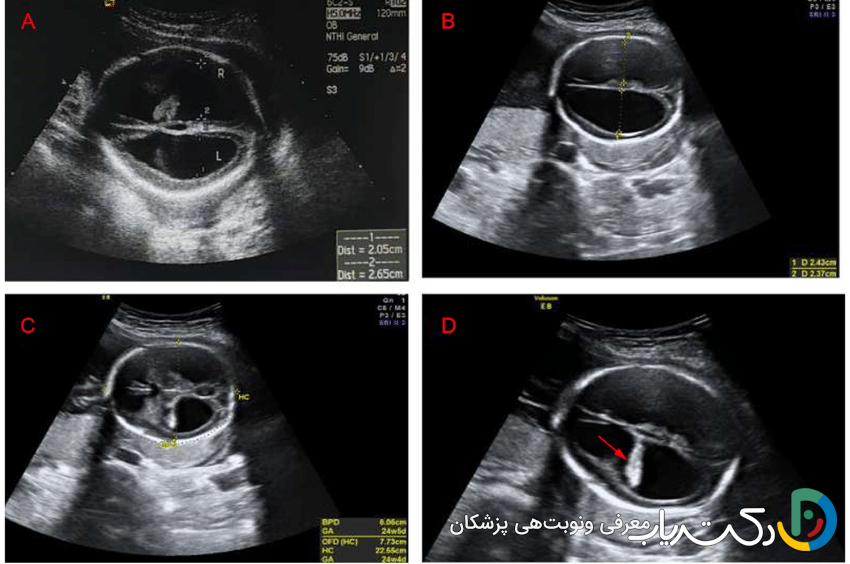

- ونتریکولومگالی: کلیدیترین یافتهای که در سونوگرافی شک به هیدروسفالی را برمیانگیزد، ونتریکولومگالی یا بزرگ شدن بطنهای جانبی مغز است. رادیولوژیست عرض دهلیز بطنهای جانبی را اندازهگیری میکند.

- اندازهگیری طبیعی: کمتر از ۱۰ میلیمتر.

- ونتریکولومگالی خفیف: بین ۱۰ تا ۱۵ میلیمتر.

- ونتریکولومگالی شدید: بیشتر از ۱۵ میلیمتر.

- اهمیت یافتهها و علائم مرتبط: تشخیص ونتریکولومگالی همیشه به معنای هیدروسفالی نیست، اما یک زنگ خطر جدی است. متخصص سونوگرافی به دنبال سایر علائم مرتبط نیز میگردد، مانند عدم وجود ساختارهای دیگر مغزی (مثل کورپوس کالوزوم) یا ناهنجاریهای ستون فقرات (مانند اسپاینا بیفیدا). این یافته نیازمند بررسیهای بیشتر مانند سونوگرافیهای هدفمند و دقیقتر، MRI جنین برای ارزیابی بهتر آناتومی مغز و مشاوره ژنتیک است تا علت زمینهای آن مشخص شود.

- تصاویر حاصل: سونوگرافی جمجمه به وضوح اندازه و شکل بطنها را نشان میدهد و میتواند وجود خونریزی ، کیست، آسیب به بافت اطراف بطنها یا سایر ناهنجاریهای بزرگ را مشخص کند.